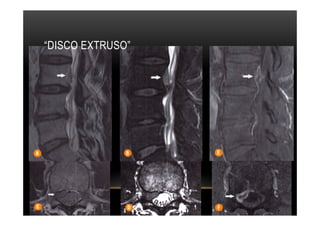

“DISCO EXTRUSO”

•  A terminologia "disco extruso" é usada para uma projeção focal do disco, em que a

base é mais estreita do que os demais diâmetros medidos no mesmo plano,

havendo rotura de todas as camadas do ânulo fibroso.

•  O material discal herniado pode migrar de forma subligamentar (superior e inferior).

•  Extrusão discal migrada se é mantido conexão com disco de origem

•  Fragmento discal sequestrado (ou livre), se não é mantido conecto com disco

de origem podendo ter sinal elevado do material sequestrado em T2 em relação

ao disco de origem.

•  Frequentemente associa-se extenso processo inflamatório adjacente ao material

discal extruso, melhor visibilizado após a injeção do meio de contraste. Referir no

laudo a integridade do ligamento longitudinal posterior, se íntegro, as herniações são

consideradas subligamentares.